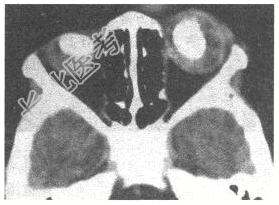

- [材料题] 男孩,2岁,双眼疼痛1年,右侧眼球突出。CT平扫如图:

- 简答题1、本病最可能诊断为?

- 简答题2、请问诊断依据是什么?

- 简答题3、为进一步确诊,需要做的检查有哪些?

- 简答题4、视网膜母细胞瘤如何治疗?